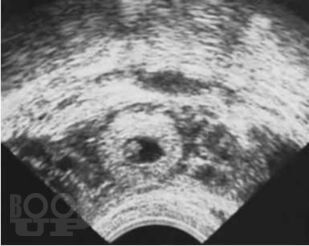

В пособии представлены данные об этиологии, современных методах диагностики и лечения внематочной беременности. Подробно изложен алгоритм обследования при внематочной беременности на различных этапах постановки диагноза, тактика ведения пациенток. В результате использования учебного пособия студенты могут овладеть следующими компетенциями: ОПК 8, 11, 12; ПК 1, 5, 6, 8, 9, 10. Предназначено для подготовки студентов IV, V курсов лечебного факультета к занятиям семинарского типа по дисциплине «Акушерство и гинекология» и составлено с учетом требований ФГОС 3++ по направлению специальности «Лечебное дело».